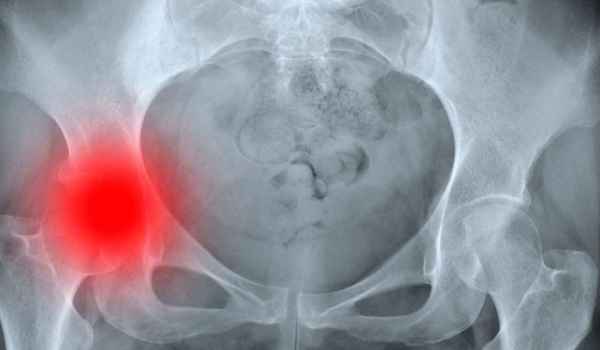

La fractura de cadera es una de las patologías más frecuentes en el anciano. Además, con grandes repercusiones sociales, sanitarias y económicas, se prevé que su incidencia vaya en aumento en los próximos años. De ahí la importancia de su prevención, en la que la enfermería tiene un papel protagonista. De hecho, el éxito de su tratamiento reside, principalmente, en su prevención primaria, pero también en la reducción de complicaciones.

Tema I. Epidemiología.

Tema II. Concepto y Generalidades.

Tema III. Etiología.

Tema IV. Factores de riesgo de fractura de cadera.

Tema V. Diagnóstico.

Tema VI. Clasificación o tipos de fractura.

Tema VII. Presentación clínica y características de los pacientes con fractura de cadera.

Tema VIII. Tratamiento.